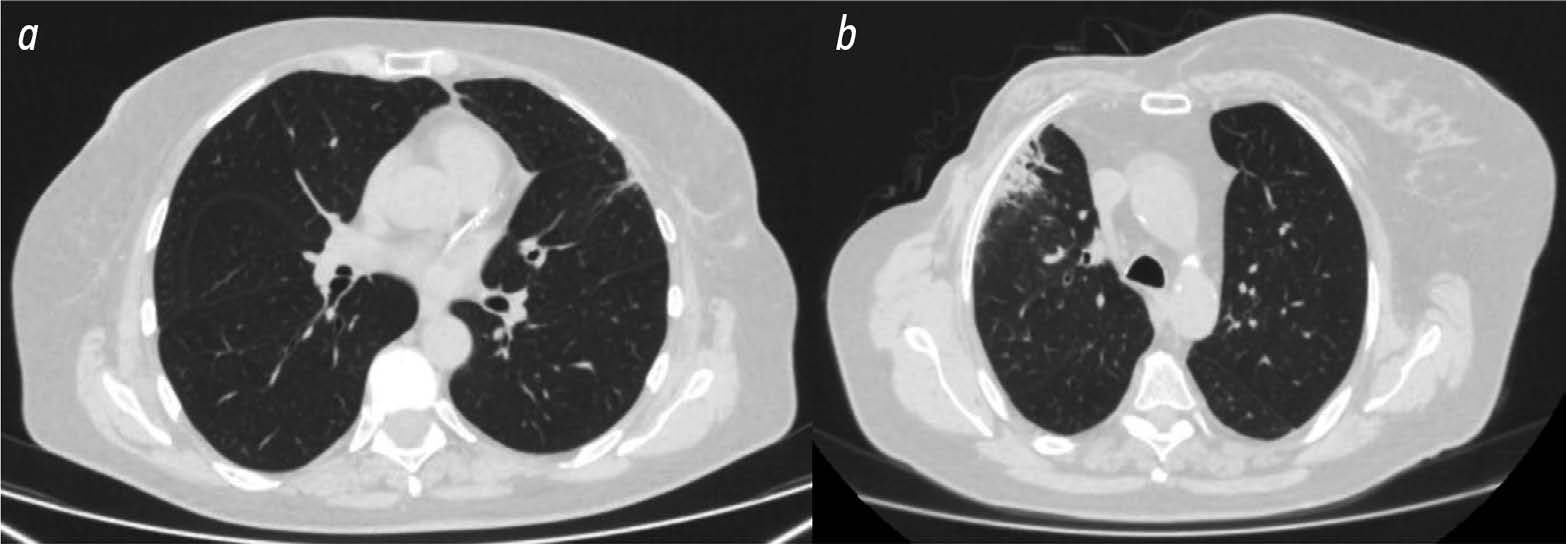

Материалы и методы. В исследовании использовали данные 36 женщин с раком молочной железы, прошедших послеоперационный курс конформной лучевой терапии. Ретроспективно пациенток разделили на две группы по степени постлучевых изменений лёгких. Результаты компьютерной томографии всех пациенток, полученные на этапе планирования лучевой терапии, и планы распределения доз облучения анализировали с помощью программного обеспечения 3D Slicer с функцией выгрузки показателей радиомики и дозиомики из областей интереса. В качестве областей интереса выбирали область мягких тканей грудной клетки и области лёгкого на стороне облучения, дозовая нагрузка на которые превышала 3 и 10 Гр.

Результаты. В первую группу включили 13 пациенток с минимальными постлучевыми изменениями в лёгких, во вторую группу — 23 пациентки с постлучевым пневмофиброзом. В области лёгкого на стороне облучения с дозовой нагрузкой более 3 Гр статистически значимые различия между группами пациенток получены по трём показателям радиомики и одному показателю дозиомики. В области лёгкого на стороне облучения с дозовой нагрузкой более 10 Гр статистически значимые различия получены по 12 показателям радиомики и 1 показателю дозиомики. В области мягких тканей грудной клетки на стороне облучения значимые различия получены по 18 показателям радиомики и 4 показателям дозиомики.

- Нуднов Н.В., Сотников В.М., Леденёв В.В., Барышникова Д.В. Возможности качественной оценки лучевых повреждений лёгких методом компьютерной томографии // Медицинская визуализация. 2016. № 1. С. 39–46. EDN: VWOIIB

- Леденёв В.В. Методика количественной оценки лучевых повреждений лёгких у онкологических пациентов по данным рентгеновской компьютерной томографии: диссертация на соискание учёной степени канд. мед. наук. Москва, 2023. 133 с. Режим доступа: https://www.rncrr.ru/nauka/dissertatsionnyysovet/obyavleniyaozashchitakh/upload%202023/Леденев_Диссертация.pdf Дата обращения: 25.11.2023. EDN: YBWROM